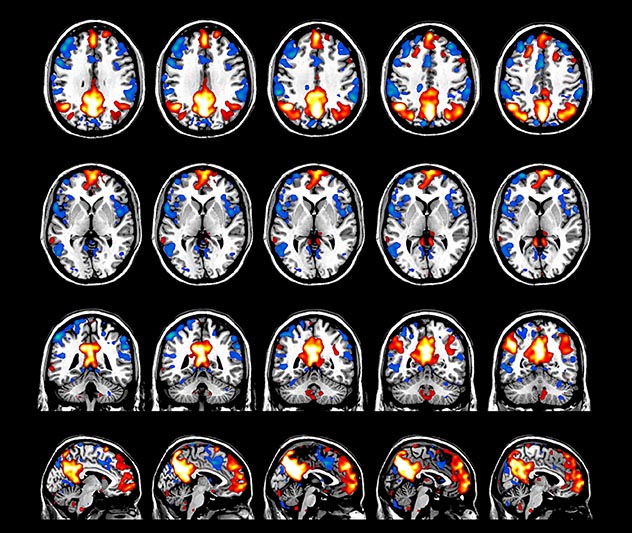

BOLD fMRI activation, depicted in color, of left anterior insula (MNI plane z = 8 mm) in a single subject by a contrast between viewing and matching faces with negative emotion (angry, sad, scared) versus happy faces. The voxelwise threshold is p < 0.001, and colored voxels survive false discovery rate correction to p < 0.05. The activated voxels in color are overlaid on the subject's own 3D-TFE image displayed in grayscale, after transforming the data to MNI space. The fMRI pulse sequence was a single shot FFE echo planar acquisition using MultiBand SENSE factor 6, dS SENSE factor 1, isotropic voxel size 2.4 mm, 60 transverse slices, TR 950 ms, TE 30 ms, flip angle 52 degrees, 517 dynamic scans, total scan duration 8:21 minutes. Image provided by James M. Bjork, PhD, Associate Professor of Psychiatry at VCU.

The fMRI pulse sequence was a single shot FFE echo planar acquisition using MultiBand SENSE factor 5, dS SENSE factor 1.25, isotropic voxel size 2.7 mm, 50 transverse slices, TR 700 ms, TE 30 ms, flip angle 52 degrees, 765 dynamic scans, total scan duration 9:01 minutes. Image provided by Matthan Caan, PhD, Assistant Professor at the AMC.

Imaging was performed using Ingenia 3T CX with a 32ch dS Head coil, TR 1.6 sec, TE 35 ms, voxel size 3.1 x 3.1 x 3.1 mm, 46 slices and Multiband SENSE factor 2. Image provided by Dr. Gispert

Default mode network as discovered by resting state fMRI in one participant of the ALFA cohort [7]. rs-fMRI allows us to find networks of brain regions with highly correlated activity and sustaining distinct brain functions. The default mode network (in warm color scale) is active when the brain is focused on introspective thinking and has been shown to be altered in Alzheimer’s. Interestingly, brain areas of this network are known to show abnormal levels of one of the pathological hallmarks of Alzheimer’s (b-amyloid deposition) in preclinical stages. We want to better understand the alterations of these brain networks in preclinical stages of Alzheimer's and explore their potential use as biomarkers.

Emotional n-back task combines a test of working memory with the use of emotive (faces) and neutral (places) images. The contrast in the images is between the activity when faces are presented compared to places, showing activation in the amygdala, fusiform, and occipital face areas.

Processing based on the Human Connectome Project (HCP) pipelines. The high resolution of the fMRI data allows extraction of the cortical surface, with minimal averaging of non-cortical signal. Surface based analysis provides improved cross-subject alignment, and prevents signal contamination between adjacent sulci.

Group analysis of 88 9- and 10-year olds part of ABCD, all scanned at UVM on Philips Achieva 3.0T dStream. Scale runs from red p=0.001 to yellow p<10ˆ-5. Images provided by Dr. Watts.

Acquisition using the ABCD protocol for fMRI with TR 800 ms, TE 30 ms, flip angle 52°, 2.4 mm isotropic imaging resolution with a 216×216×144 mm3 field of view using a MultiBand acceleration factor of 6 (60 slices, no gap). Two runs of 5 minutes per subject.